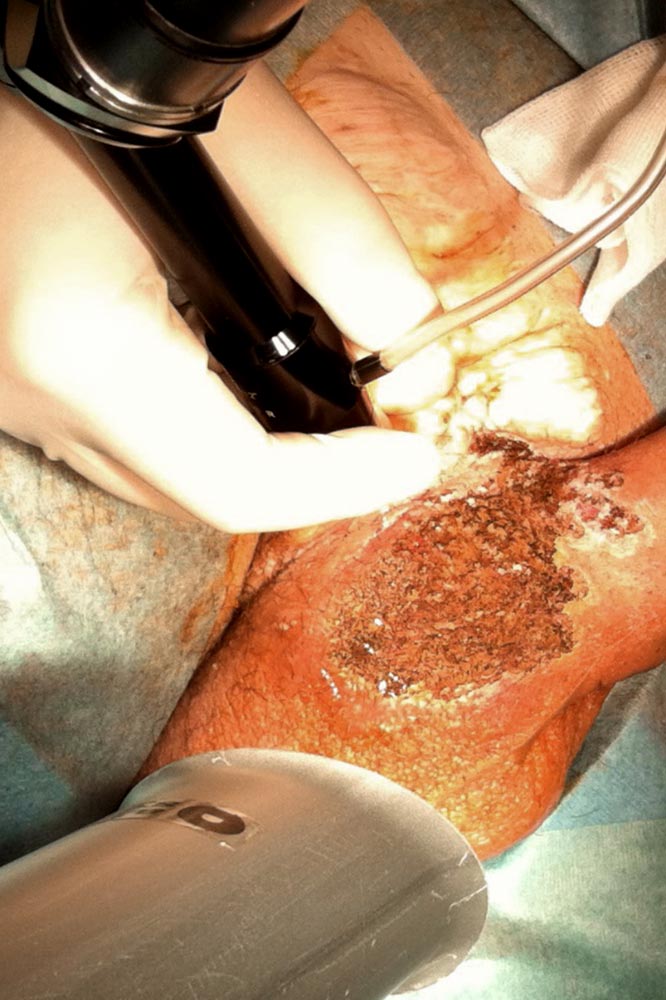

Small cutaneous lymphatic vesicles, lymphangioma circumscriptum, especially with accompanying lymphatic leakage (lymphorrhea), can be a good indication for CO2 laser treatment. This leads to complete thermal ablation of the upper skin layers. It often results in initial sealing of the lymph flow from the skin and the formation of a skin scar. Unfortunately, local recurrences are also relatively common.

If the lesion does not completely regress, sometimes the dot-like application of the laser spots without overlap may result in conspicuous geometric patterns of the skin. As a thermally destructive procedure, circumscribed tissue destruction may also occur. On the skin, these includes localized blisters to wounds, discoloration, pigmentary shifts, localized skin atrophy, and scabbing. In the case of deep, interstitial application, for which a circumscribed volume is heated, nerve injuries, burns and, above all, scarring in the course of treatment have also been described. Recurrences are possible.